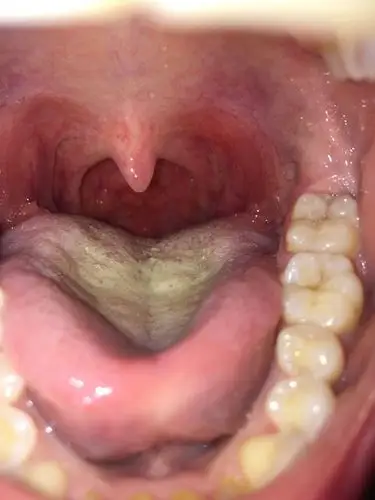

咽部充血

扁桃体发炎了没? 特疼,咽口水都痛,耳朵也有点疼,听力好像也不太好了.

请问这属于扁桃体发炎吗?

发烧两天 现在不发烧了 嗓子充血 疼 有点痒 咳嗽

喉咙充血,干,不痛有一个月了,打针吃

一个月前感冒了,过了一周就好了,后来扁桃体一直隐隐约约有点肿,但是

我做过扁桃体手术,我发现我咽道壁上长满水泡一样的东西是什么,会变成